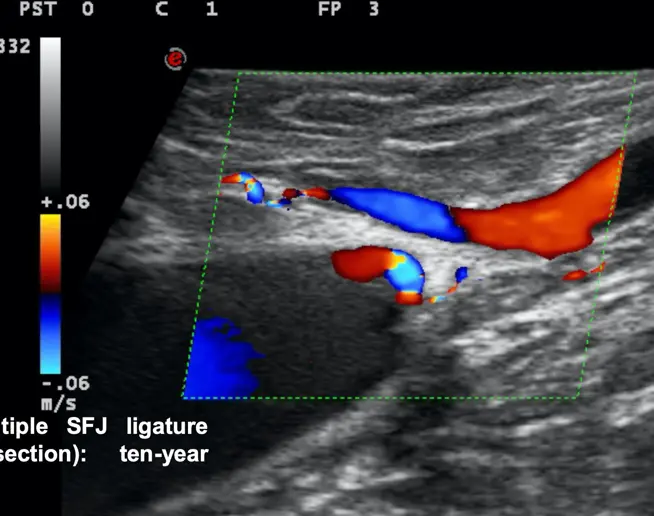

在局部麻醉下进行的微创手术,并配合术前B超定位标记。

该治疗高度根据每位患者的分流类型进行个性化设计。